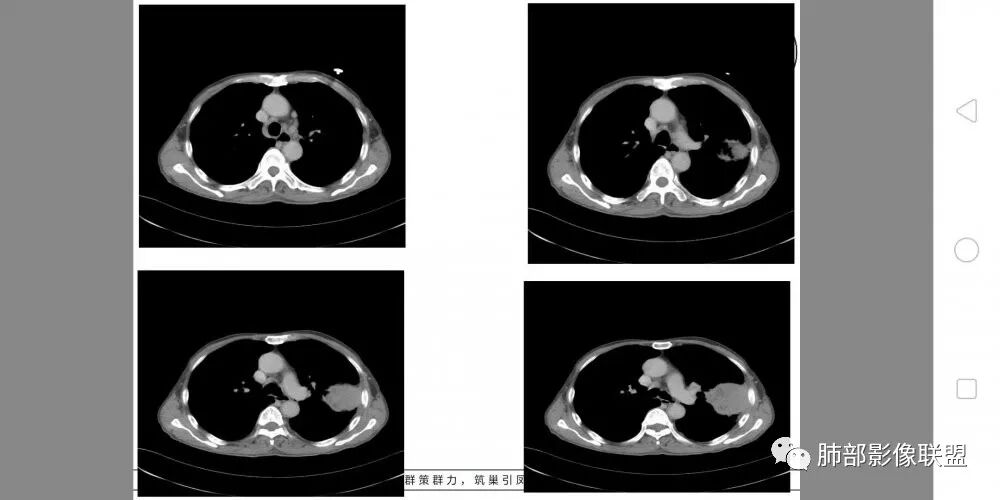

老年男性,外伤入院,“左上肺”实性肿块,边缘光滑,突破壁层胸膜并侵犯肋骨及肋间肌,增强扫描轻度强化,可见明显坏死。

左肺上叶实性肿物,左肺上叶支气管受压变窄,病灶边缘光滑,轻度分叶,病灶轻度强化内部可见多发小灶坏死,坏死边界模糊,病灶突破壁层胸膜侵及左侧部分肋骨及肋间肌,考虑恶性,肉瘤样癌,鉴别诊断低分化腺癌。

• 胸CT:左肺上叶实性占位,病灶与支气管无关,病灶对斜裂挤压,病灶周围光滑,未见分叶、毛刺;纵隔窗可见病灶内低密度区,病灶对胸壁侵袭,并可见肋骨破坏。

胸CT:左上肺实性大肿块,边缘光滑,突破胸膜侵犯肋骨及肋间肌,纵隔淋巴结肿大,增强呈轻度强化,可见明显片状坏死。

胸部CT所见左肺上叶尖后段胸膜下较大山丘形肿块,边界清楚,宽基底与胸膜相贴,边缘与胸膜呈直角及锐角相交。邻近上叶尖后段支气管受压推挤,叶裂局部膨隆,病灶周围见少许磨玻璃密度影,边界不清。纵膈窗显示,肿块密度均匀,增强扫描呈不均匀轻度强化,邻近肋骨骨质破坏,病变沿肋间隙向外侵犯,局部胸膜增厚。纵膈内见多发小淋巴结,未见胸腔积液征象。综合考虑恶性占位,肉瘤样癌可能性大。腰椎及髋部考虑骨转移。

综合考虑恶性肿瘤,外朝内发展,倾向于肺内来源。

鳞癌,与吸烟关系密切,起源于支气管粘膜上皮,典型的征象就是支气管截断,周围型鳞癌往往体积较大,有时候与支气管关系不好判断,需要多平面重建看支气管的关系。

鳞癌因为侵袭性力较强,容易直接侵犯胸膜、胸壁,而周围型肺癌侵犯胸壁的90%癌肿是鳞癌,这也是鳞癌的一个特征性表现。邻近胸壁的脂肪层消失,胸壁肿块形成或有肋骨皮髓质边界不清的侵蚀破坏(而非边缘硬化或崩解)是瘤体向周围直接侵犯的可靠征象。

肉瘤样癌也好发于中老年人,与吸烟关系密切。肿块体积往往较大,也是好发于胸膜下伴胸壁侵犯,也容易发生坏死,与周围型鳞癌的主要鉴别点在于支气管的关系和病灶内强化的情况。肉瘤样癌以环状强化为主,病灶周边多以癌组织为主,血供丰富,病灶中心区则以肉瘤成分为主,血供较差,易出现粘液样变性、坏死、出血,坏死边界清楚。